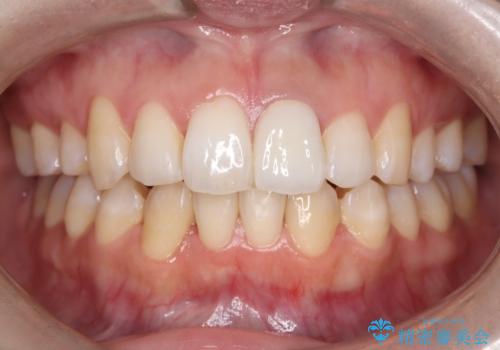

オールセラミッククラウンによる修復: 最終的な被せ物には、一切の金属を使用しないオールセラミックを選択。隣の天然歯と色調や透明感を精密に合わせることで、どこを治療したかわからないほど自然な仕上がりとなりました。